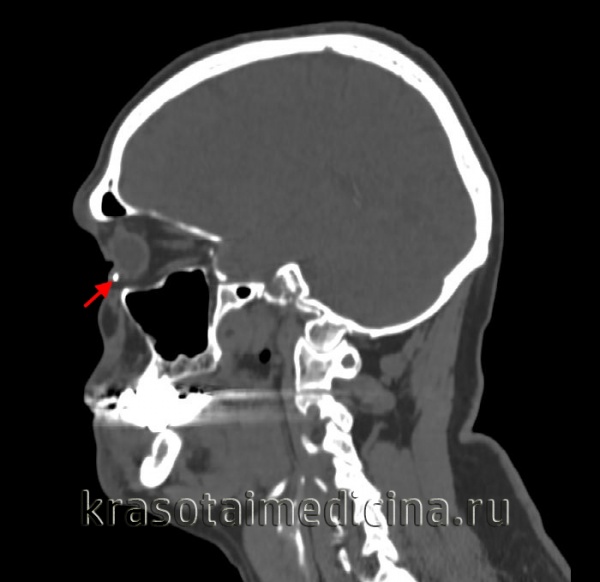

- УЗИ глаза. Позволяет визуализировать инородное тело в полости глазницы, а также изменения заднего полюса глазного яблока при помутнении хрусталика. Определяется неоднородная эхогенная структура оптических сред.

- Рентгенография орбиты. Позволяет выявить рентгеноконтрастные инородные частицы, установить их локализацию и характер повреждения костных стенок.